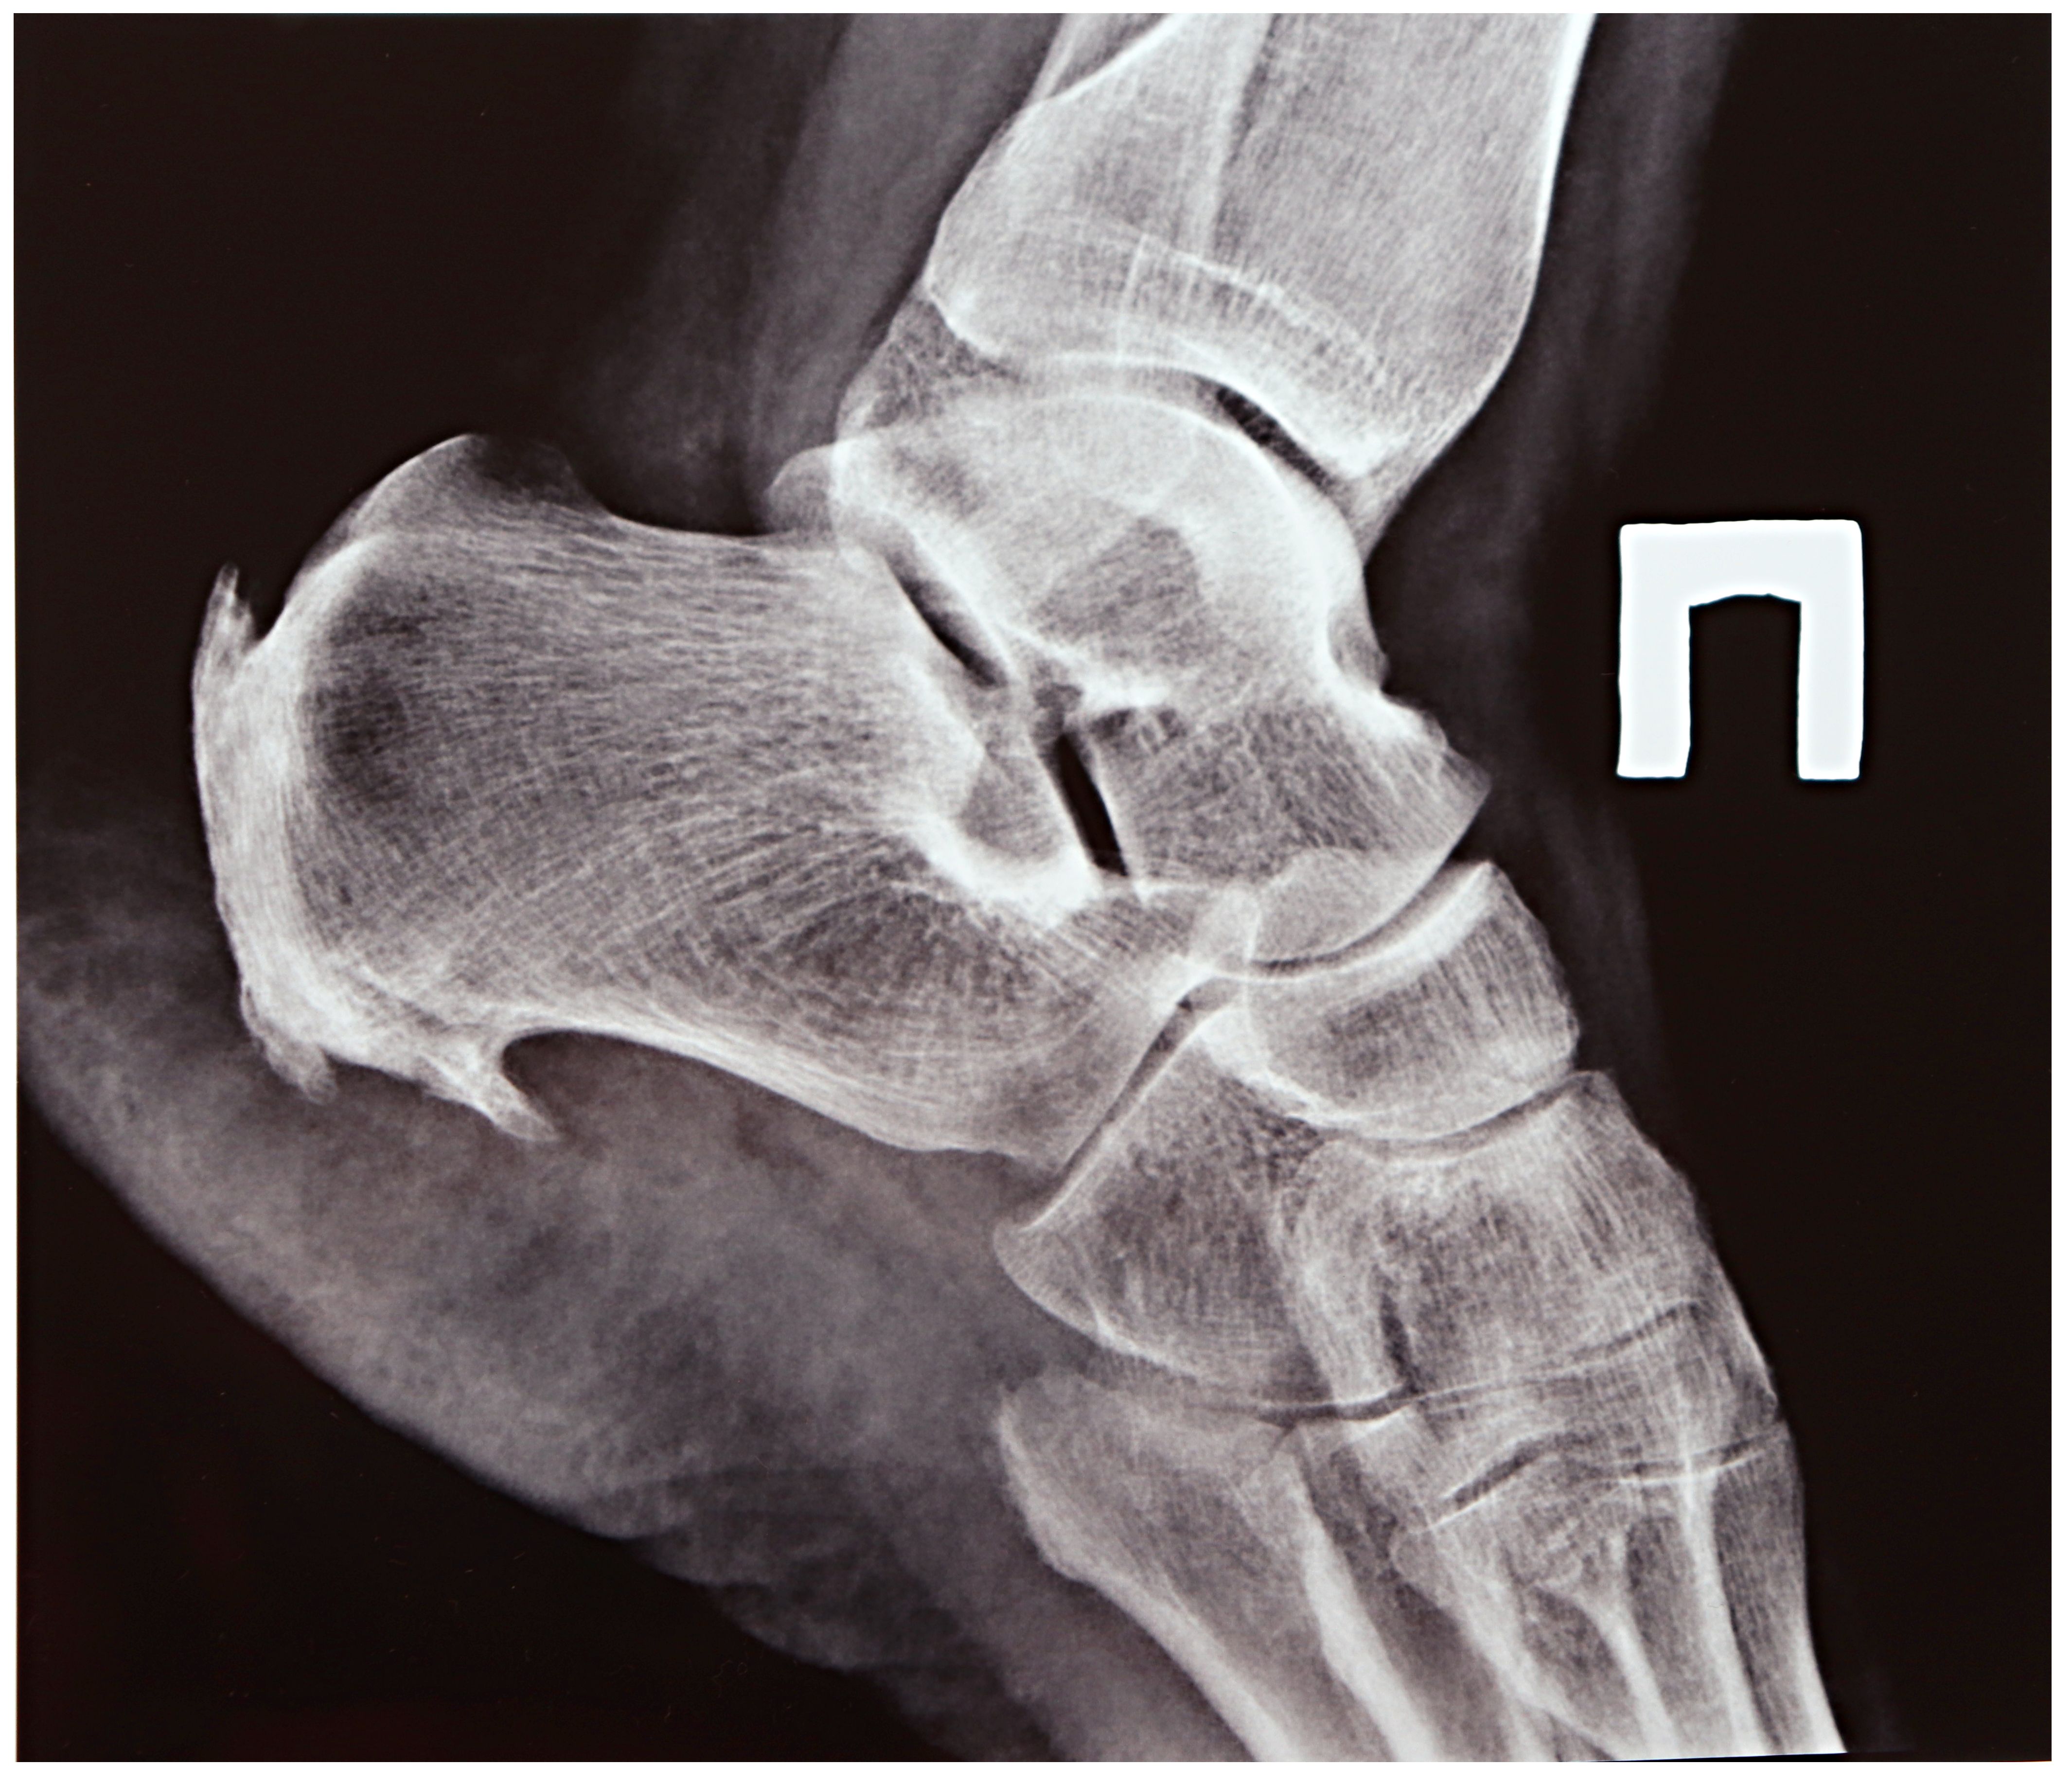

Heel spurs are often misunderstood and surrounded by myths that can lead to unnecessary worry. A heel spur is a bony growth on the underside of the heel bone, often associated with plantar fasciitis. They are common among athletes, particularly those who engage in running or jumping activities. Despite their prevalence, many misconceptions exist about their causes and treatments.

One of the most common myths is that heel spurs are the primary cause of heel pain. However, research shows that heel spurs themselves are often painless. The discomfort usually stems from inflammation of the plantar fascia, a thick band of tissue that runs across the bottom of the foot, connecting the heel bone to the toes. Heel spurs can be present without any pain, and not everyone with plantar fasciitis has a heel spur.